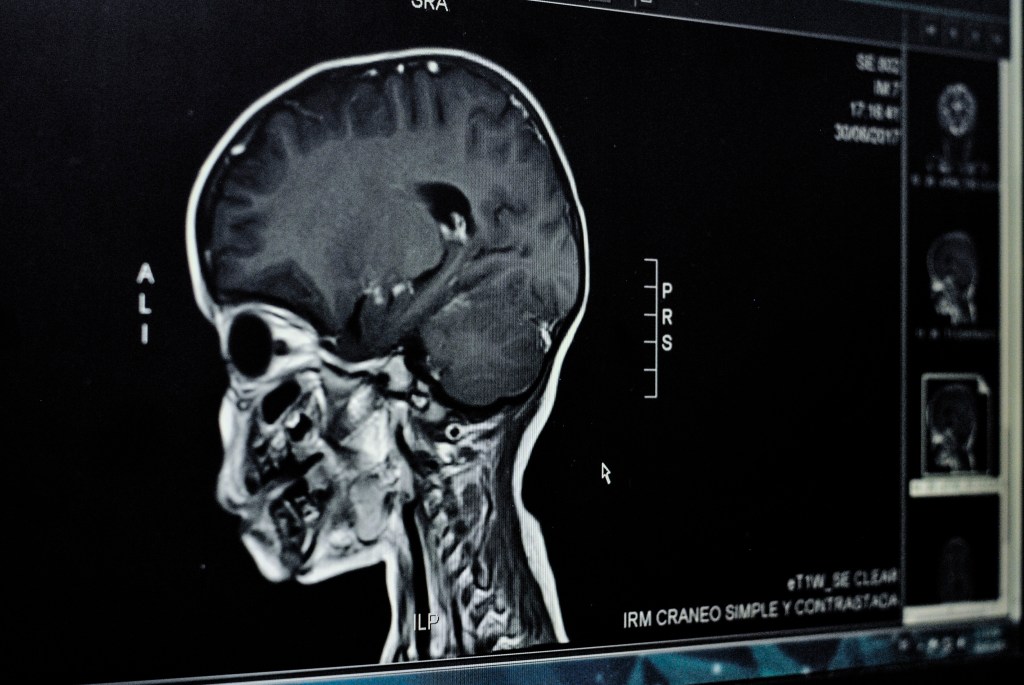

Healthcare startup Lyfebin exposed thousands of medical imaging files, such as X-rays, MRI scans and ultrasounds.

The storage bucket contained more than 93,000 files — many appeared to be duplicates — containing medical scans. The files were stored in the DICOM format, a common file type used by medical imaging equipment. When opened, DICOM files contain the images from the scan as well as other metadata, such as the patient’s date of birth and the name of the physician.